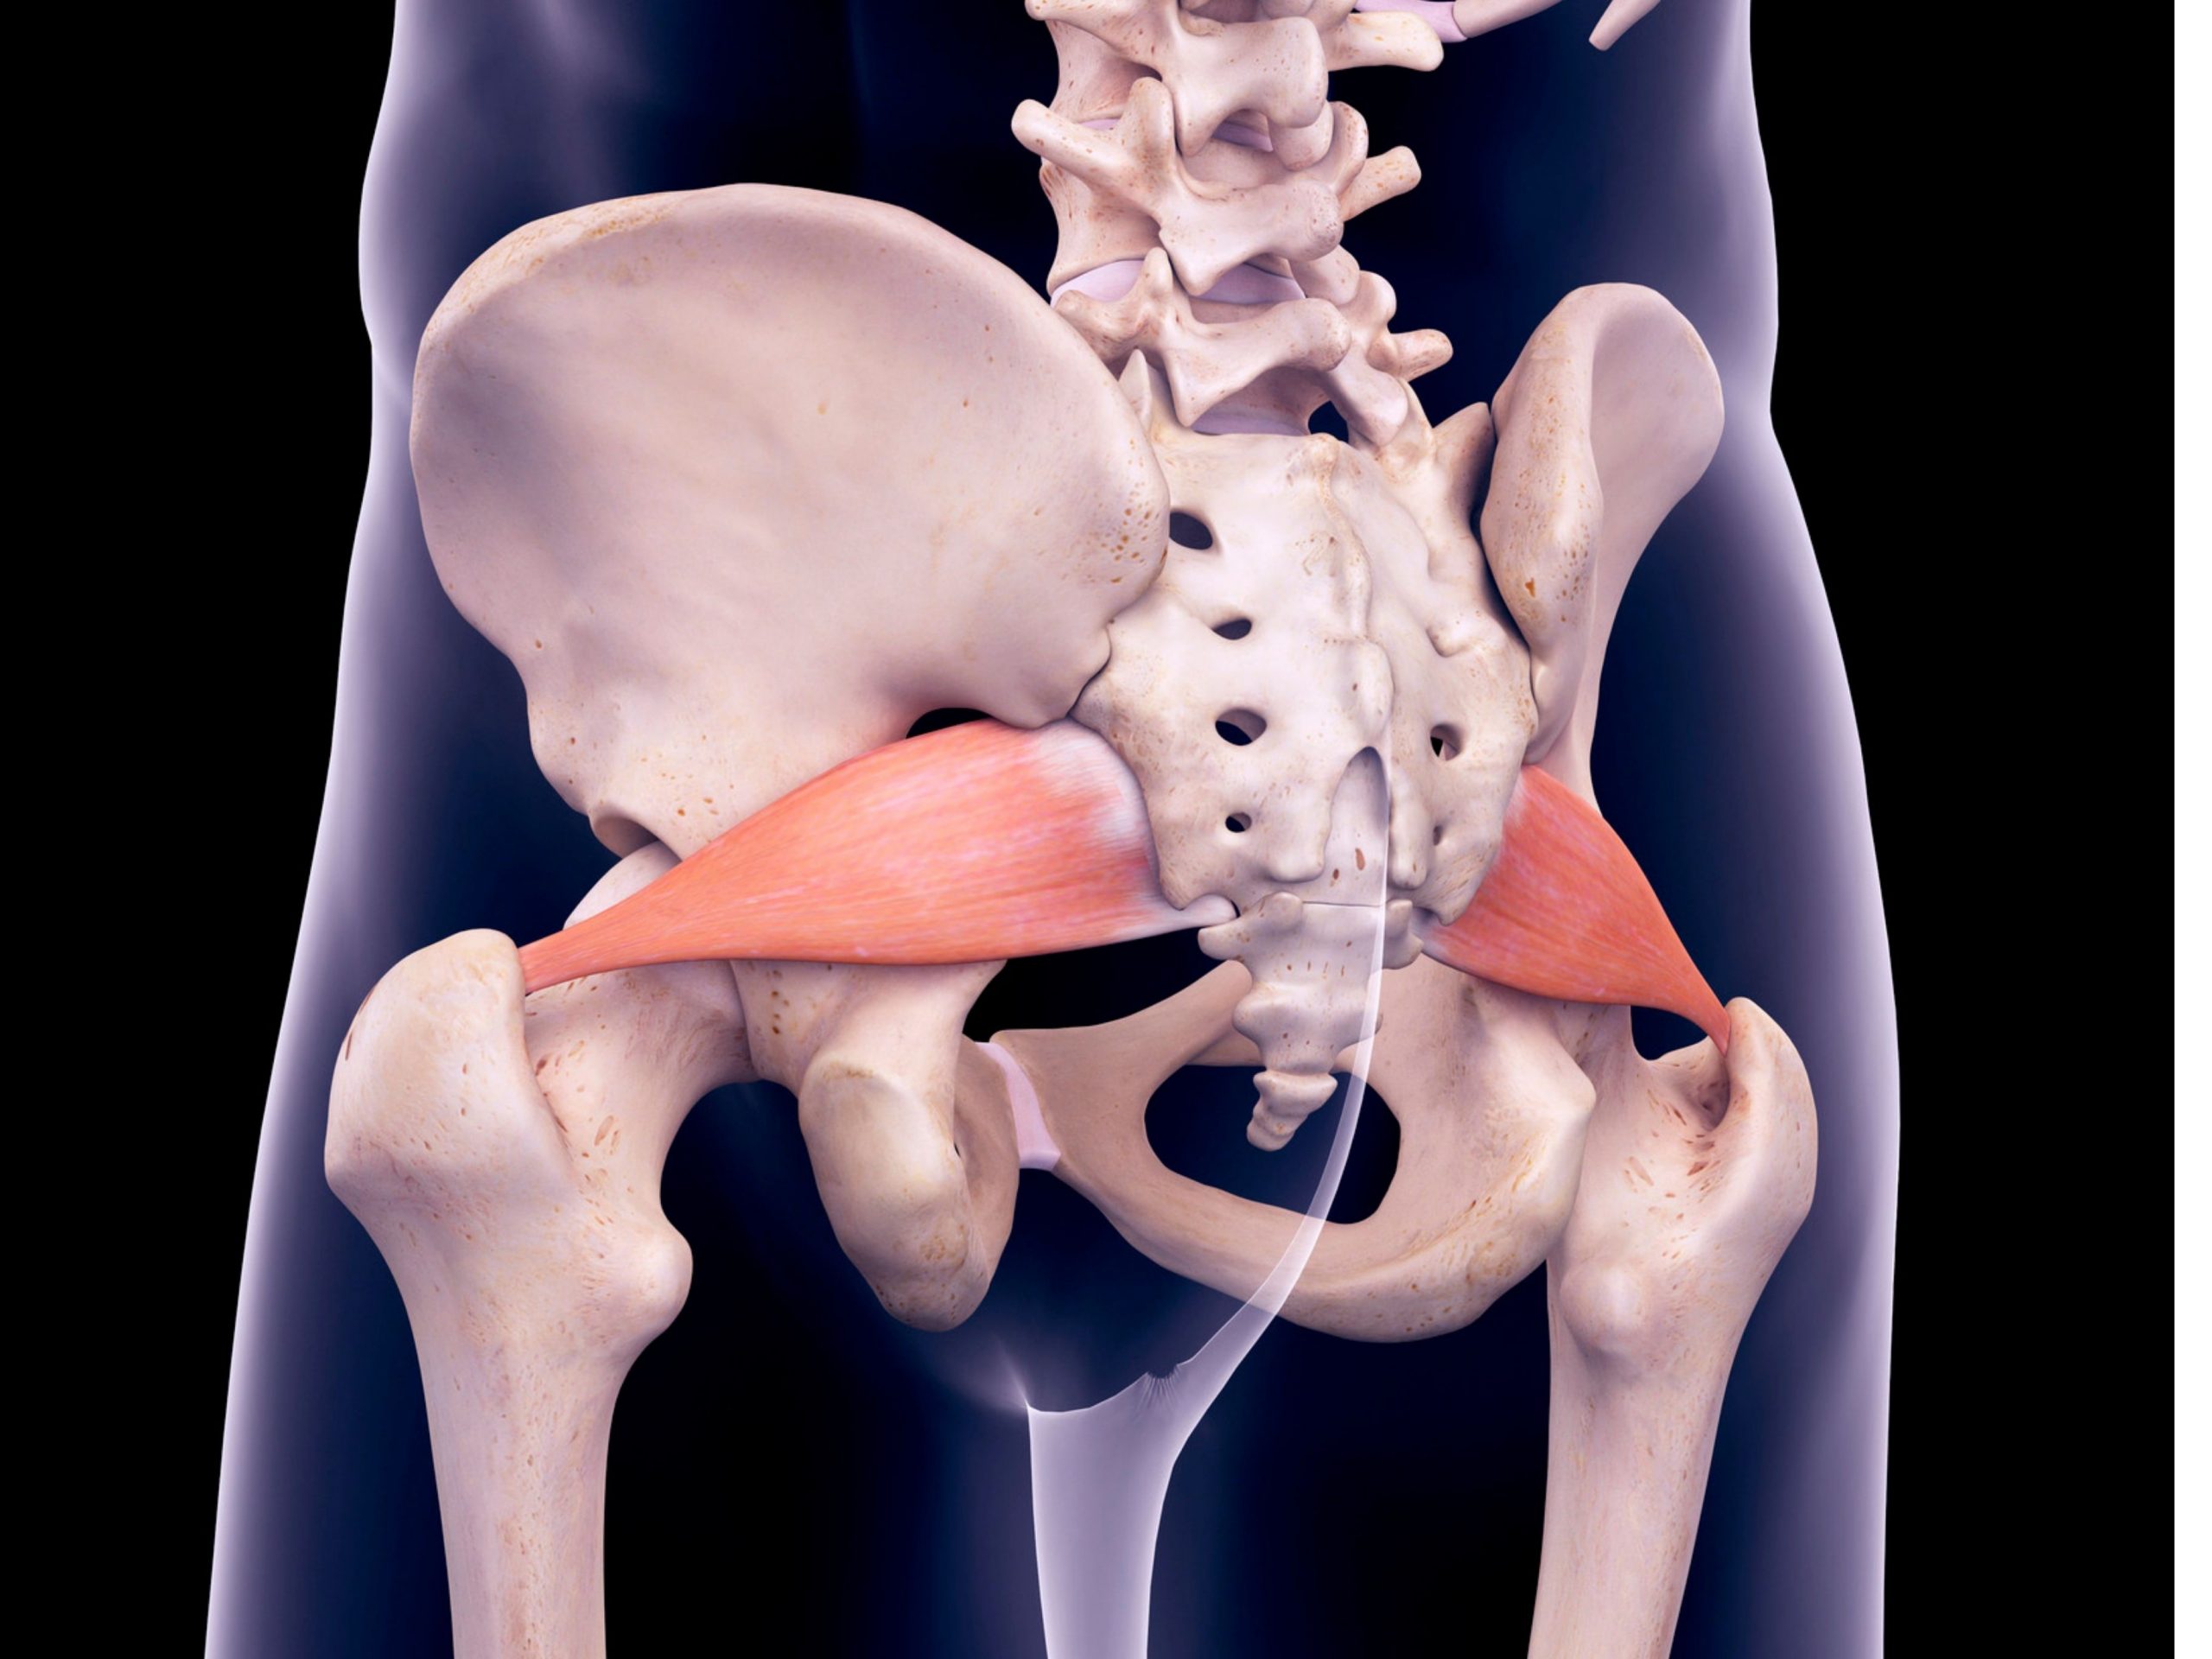

Анатомия мышц: Пириформис